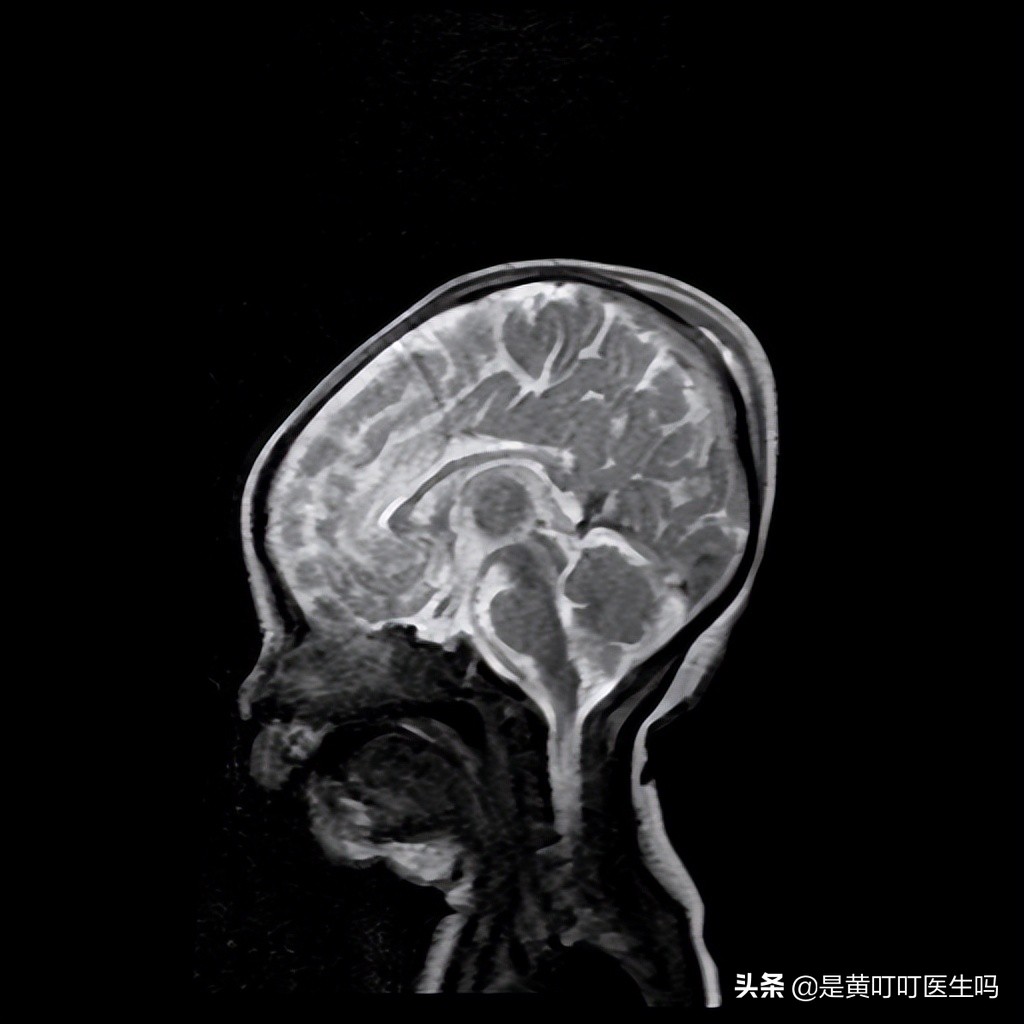

影像学检查(CT、MRI)有助于判断产瘤的性质——水肿还是血肿,是否合并颅内出血。

磁共振下的产瘤